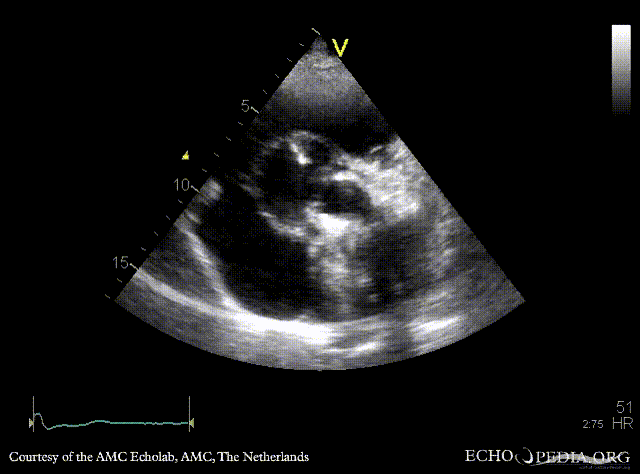

Case 37

Abscess of aortic root

Courtesy of: AMC Echolab, AMC, The Netherlands

E00271.gif E00272.gif

PSAX: abscess of aortic root A4CH: large abscess of aortic root